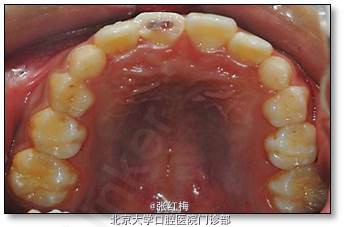

11牙冠龈1/3折断,牙髓暴露约6×1mm2,灰紫色,略有增生,叩(±),不松,龈未见异常,

21牙冠龈1/3釉质横形隐裂,叩痛(-),不松,冷测同正常对照牙,龈未见异常;

X线示:11、21发育9期,根管粗大,未见明显根折线,根尖周未见病变影,骨硬板清晰,未见牙槽突骨折线;